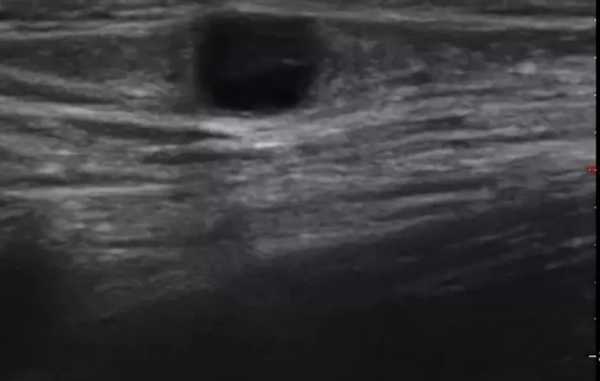

Практически во всех случаях дифференцировали лимфатический узел Кютнера (югулодигастральный), расположенный на границе средней и верхней трети шеи. Выявляемые лимфатические узлы имели размеры от 0,5 х 0,2 см до 2,3 х 0,8 см. УЗ-оценку производили после полипозиционного осмотра и нахождения самой длинной горизонтальной оси, что и принимали за максимальный поперечный диаметр. Большая часть лимфатических узлов (187) имели овальную форму с соотношением поперечного/переднезаднего более 1 (рис. 1 - 3). Тенденцию к округлению имели 30 лимфатических узлов, соотношение поперечного/переднезаднего приближалось к 1.

Рис. 1. УЗ-томограмма увеличенного реактивно измененного лимфатического узла: а - на фоне аденовирусной инфекции, б - после проведения противовоспалительного лечения

Рис. 2. Эхографическое изображение непальпируемого югулярного лимфатического узла на фоне остаточных явлений после перенесенного фарингита.

Рис. 3. Эхографическое изображение непальпируемого югулярного лимфатического узла без четкой клинической симптоматики воспалительного процесса в области головы и шеи.

Мы установили, что, как правило, более округлая конфигурация лимфатического узла при его размерах, превышавших 10 мм, сопровождалась небольшими болевыми ощущениями, и более выраженной простудной (воспалительного характера) симптоматикой. Лимфатические узлы менее 10 мм чаще всего плохо пальпировались, либо вообще не выявлялись пальпаторно. Во всех случаях эхографически хорошо дифференцировался гипоэхогенный кортикальный слой и широкое, средней или чуть ниже средней эхогенности изображение области ворот лимфатических узлов. Четкость дифференциации составных частей лимфатического узла была снижена при размерах менее 5 мм. Мы отмечали различную толщину гипоэхогенного изображения области коры лимфатического узла: от очень широкой - при выраженности или прогрессировании воспалительного процесса, до узкой - на фоне положительной динамики.